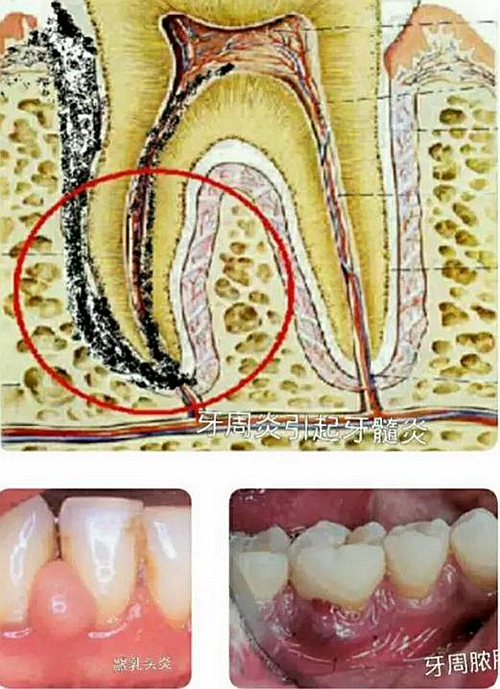

這需要與齲齒引起的牙髓炎,根尖炎時的巨痛作比較。如上組圖之上圖,齲齒是在堅硬的牙齒上面形成的,然后波及到牙神經(jīng)后引起炎癥,再向牙根方向擴散。這個過程都是在一個相對密閉的堅硬牙齒和骨頭結(jié)構(gòu)里發(fā)生和進行,迅速產(chǎn)生的大量炎癥產(chǎn)物形成巨大壓力,引起牙神經(jīng)或骨神經(jīng)巨痛。

如上組圖之下圖,為牙周病發(fā)生發(fā)展的情形。病程一般從牙齦開始,牙齦是軟組織,牙齦與牙槽骨組合的是相對開放的結(jié)構(gòu)。當(dāng)發(fā)生炎癥時,炎癥產(chǎn)物形成的壓力一般較小,加之漱口,喝水以及唾液流動等,又能沖洗稀釋,所以牙周組織發(fā)炎時,多數(shù)情況下,不會引起巨痛。

牙周病雖然大多時候癥狀輕微,但也有發(fā)生劇痛的時候,如上組三圖所示,比如發(fā)生齦乳頭炎,牙周膿腫及牙周炎引起牙髓炎時。此時患者必然會去看牙醫(yī)的,因為真的很疼,但是大多數(shù)患者寧愿選擇相信這些只是局限性牙病,而不愿去想,其實這是全口牙周病在局部的急性發(fā)作反應(yīng)。因此再次錯過治療控制的機會。